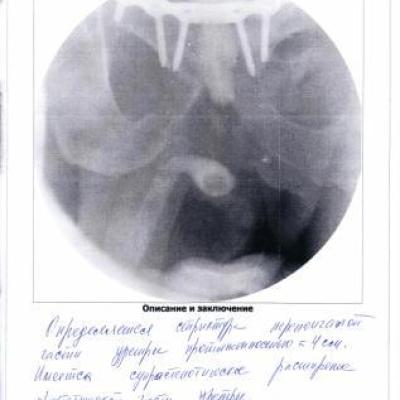

В сентябре 2014 г. меня сбила машина. Сломан таз с разрывом уретры.

В марте 2015 г. я был обследован в урологическом отделении Новосибирской больницы.

Необходима операция по восстановлению уретры.

Приложение: Выписки из истории болезни и уретроцистоскопия.